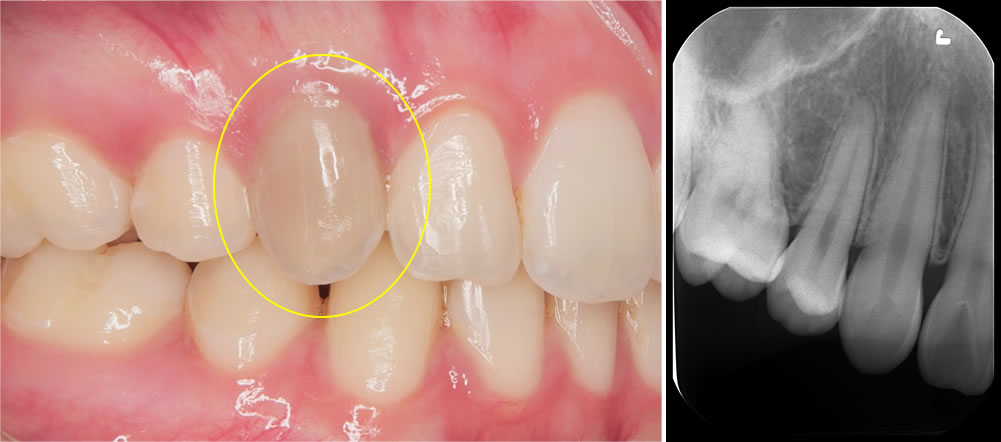

こちらの患者さんは、右上の前歯の色が黒くなってきたことを主訴に来院されました。

写真の通り、この歯だけが変色しており、他院では「削って被せ物にする必要があるかもしれない」と説明を受けていたそうです。

当院ではまず原因を調べるために各種検査を行いました。その結果、右上の前歯は冷たい刺激に反応せず、神経が死んでしまっている(失活歯)と判断しました。

原因として考えられたのは、過去に行われた矯正治療です。歯の根が骨の外に出てしまっており、本来は骨の中に位置すべき歯根が露出していたため、神経がダメージを受けてしまったと考えられます。通常、歯は骨のアーチの中に適切にコントロールして並べることが非常に重要で、それを外れてしまうと神経が死んでしまうリスクが高まります。

しかし当院では、患者さんの歯をできるだけ守るため、削らずに漂白する「インターナルブリーチ」を提案しました。歯の内部に過酸化水素の薬剤を入れることで、神経が失活して黒くなった歯でも内側から白くすることができます。

今回の患者さんも2回の薬剤の交換(約2ヵ月)の治療で歯の色が完全に回復し、自然で美しい白さを取り戻すことができました。患者さんからも「こんなに白く戻ると思わなかった」と非常に満足していただけました。